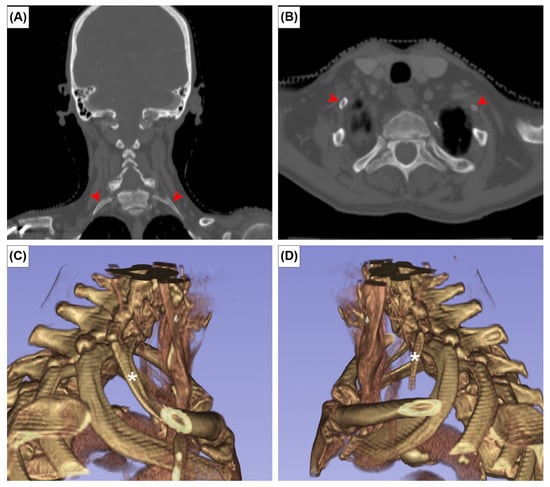

The EOs were present at the posterior surface of the manubrium in 12 cases (2.0%). It was unilateral in seven sterna (58.3%) (Figure 2A,B) and bilateral in five (41.7%) (Figure 2C). The CR was found bilaterally in one patient (0.2%) (Figure 3). In this patient, the left CR was approximately 40 mm long and did not articulate with any other structure. The right CR was approximately 60 mm long. It coursed anteriorly and inferiorly to reach the manubrium, but did not articulate with it.

Figure 2. Axial CT images (A,C,E) and 3D reconstruction in anterior view of (B,D,F) the episternal ossicles, left-sided (A,B), right-sided (C,D), and bilateral (E,F) types. Red arrowheads indicate the episternal ossicles.